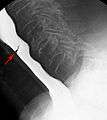

Esophageal web stenosis in barium swallow examination frontal view.